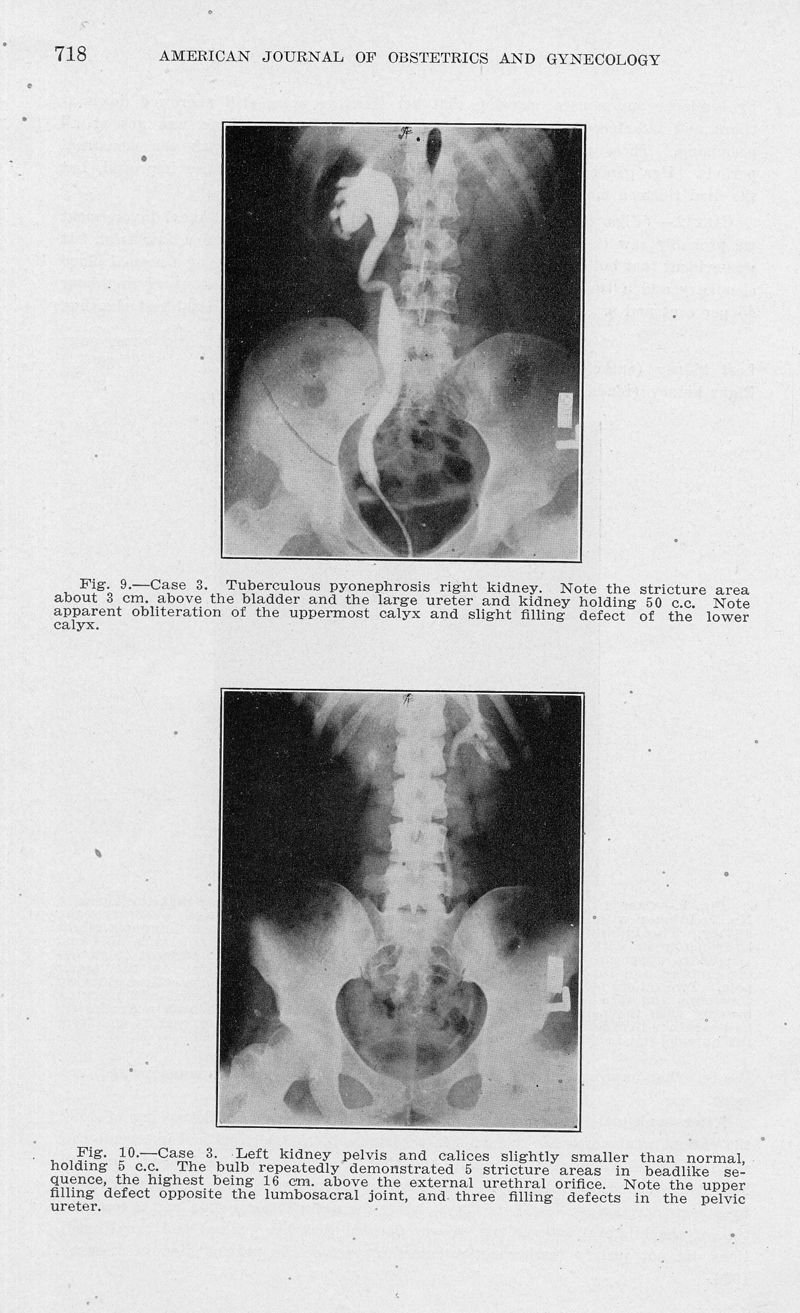

Consideration of a new viewpoint on the etiology of renal tuberculosis in women

In : American journal of obstetrics and gynecology, 1932, Vol. 24, pp. 706-28